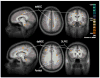

Functional and structural neuroimaging have identified abnormalities of the brain that are likely to contribute to the neuropathophysiology of attention-deficit/hyperactivity disorder (ADHD). In particular, hypofunction of the brain regions comprising the cingulo-frontal-parietal cognitive-attention network have been consistently observed across studies. These are major components of neural systems that are relevant to ADHD, including cognitive/attention networks, motor systems, and reward/feedback-based processing systems. Moreover, these areas interact with other brain circuits that have been implicated in ADHD, such as the "default mode" resting state network. The ADHD imaging data related to cingulo-frontal-parietal network dysfunction will be selectively highlighted here to help facilitate its integration with the other information presented in this special issue. Together, these reviews will help shed light on the neurobiology of ADHD.